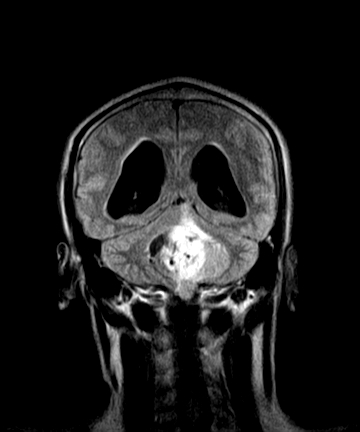

四脑室区见混杂信号占位影,脑室系统扩张明显,临近结构显著受压称位,患者52岁,多考虑室管膜瘤可能性大

考虑第四脑室室管膜瘤并阻塞性脑积水。

应该是来源于小脑蚓部的占位,如血管母细瘤或星形细胞瘤

小脑血管母细胞瘤.并外压性脑积水.

小脑蚓部胶质脑膜瘤突入四脑室;肿瘤内见血管流空信号和钙化信号.

比较典型的脉络丛乳头状瘤并脑积水,鉴别小脑蚓部血管母细胞瘤。